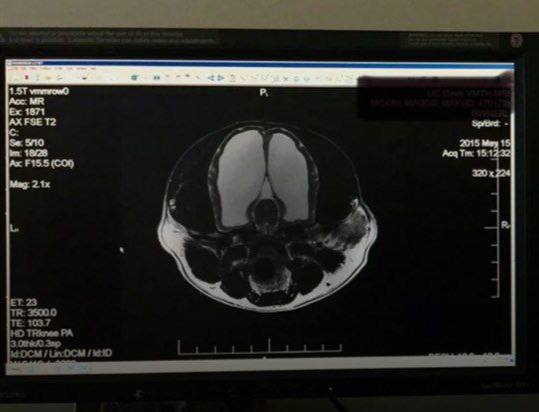

МРТ показало, что у собаки сохранилось лишь 5% мозга. Несмотря на это, она жила полноценной жизнью и даже оставила потомство.

Хозяин собаки был шокирован, когда узнал, что у его питомца почти отсутствует мозг. МРТ показало, что сохранилось лишь около 5% мозговой ткани. 🧠

Несмотря на это, собака жила обычной жизнью: бегала, играла и даже успела оставить потомство. Врачи, обнаружившие аномалию после первых припадков, могли лишь рекомендовать поддерживающий уход.